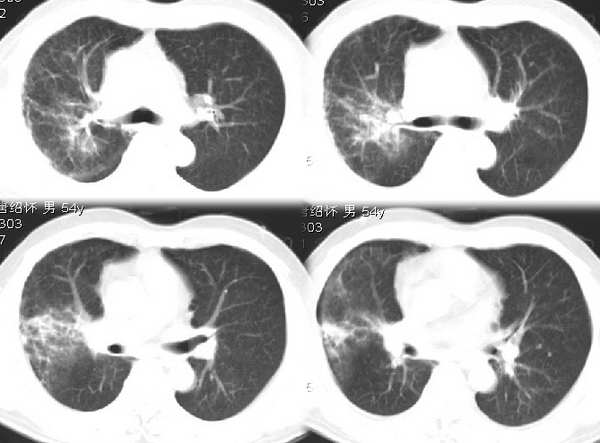

男54岁咳嗽咯痰2w,外院胸片示“右上大叶性肺炎抗炎治疗后部分吸收

右肺上叶少量间质炎性表现,结合病史为大叶性肺炎未吸收完表现。

该病人54岁,胸膜下可见多个类圆形透亮影,是不是还要考虑慢性/弥漫性肺疾病可能?

请问右中叶支气管开口旁不强化结节影是什么?

右上叶支气管变窄.ca?

右肺上叶少量间质炎性表现,大叶性肺炎吸收期。

考虑还是弥漫性间质性改变伴右肺炎症